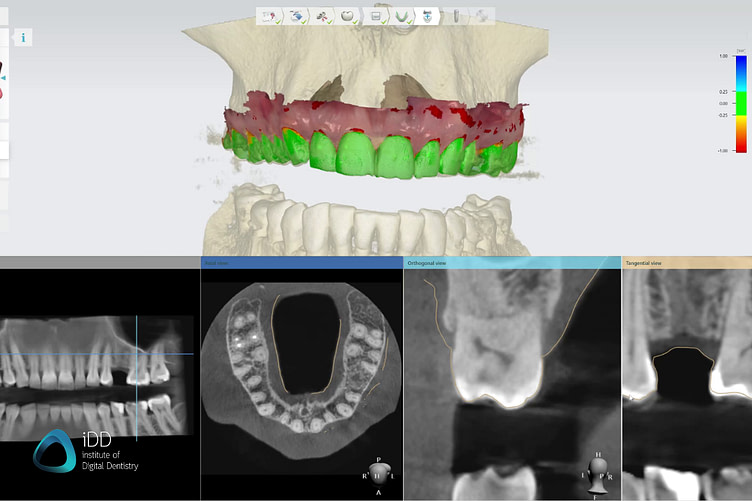

To create a surgical guide, precise digital models of the patient's oral structures are needed, both surface and internal. Intraoral scanning enables the capture of accurate digital models of the patient's dentition and surrounding tissues. Cone beam computed tomography (CBCT), provides comprehensive 3D models of the patient's bone structures. This data will be important for assessing the ideal implant position with regard to the patient’s anatomy.

Patients’ CT scans with intraoral scans should provide enough information for safe and functional implant placement. Software: 3Shape Implant Studio.

For a restorative-driven workflow, a digital tooth mock-up is used to help find the most aesthetic and functional implant position. CBCT data help you account for bone density, sinus, or inferior alveolar nerve.